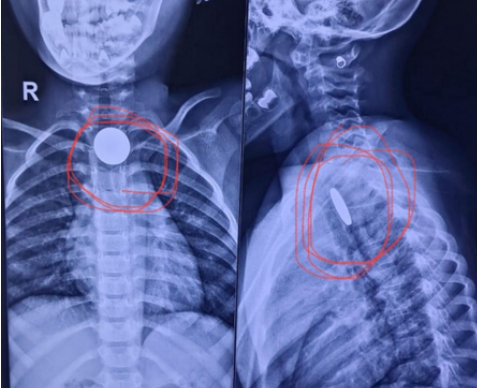

स्थिति गंभीर थी, क्योंकि सिक्का श्वसन नली के करीब अटक गया था, जिससे सांस रुकने का खतरा था। हालांकि डॉक्टरों की टीम ने ऑपरेशन कर बच्चे की आहार नली से सावधानीपूर्वक सिक्का निकाल लिया। दूसरा मामला साढ़े चार साल के एक बच्चे का था, जिसने खेल-खेल में सिक्का निगल लिया था। कुछ ही देर बाद बच्ची को गले में दर्द और खाना निगलने में परेशानी होने लगी। परिजन उसे सिविल अस्पताल लाए, जहां ईएनटी विशेषज्ञों ने एक्स-रे द्वारा स्थिति की पुष्टि की।

डॉक्टरों ने सावधानीपूर्वक बच्चे की आहार नली से सिक्का निकाला। डॉ. गज्जर ने बताया कि इस तरह के मामले छोटे बच्चों में अक्सर देखने को मिलते हैं, खासकर तब जब उन्हें सिक्के, बटन या खिलौनों के छोटे हिस्से खेलने के लिए दिए जाते हैं। उन्होंने कहा कि माता-पिता को चाहिए कि वे छोटी वस्तुएं बच्चों की पहुंच से दूर रखें। तीन से पांच वर्ष की उम्र के बच्चों को वस्तुओं को मुंह में डालने की आदत होती है, जो कभी-कभी जानलेवा साबित हो सकती है। अस्पताल प्रशासन ने दोनों मामलों में टीम की तत्परता की सराहना की और अभिभावकों को सलाह दी कि ऐसे मामलों में घरेलू उपायों पर निर्भर न रहें। अगर बच्चा कोई वस्तु निगल लेता है तो तुरंत नजदीकी अस्पताल में पहुंचें, क्योंकि थोड़ी सी देरी भी बड़ी दुर्घटना का कारण बन सकती है।